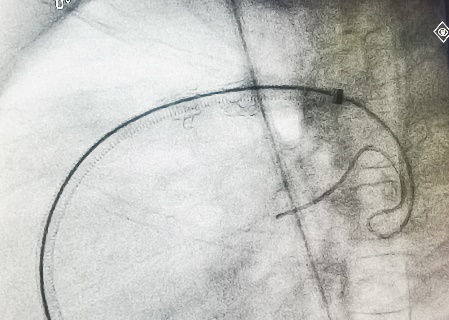

在导丝引导下,右心导管通过断裂的支架,到达左肺动脉远端。再沿导丝送入Pul-Stent,和球囊载体,覆盖断裂的支架。

术中植入Pul-stent S20支架(EV3 10-3和12-3球囊)

3.后续治疗:因病人左肺发育较差,过度扩张容易造成肺血管破裂出血,或原断裂支架的钢丝刺破肺血管,所以计划待患者左肺动脉发育以后,再次高压球囊进行扩张。Pul-Stent肺动脉支架是由钴铬合金制成,半开环的设计,可进行二次扩张,适合那些随着生长发育以后需要再次扩张的患者。

2021年5月18日,支架术后2个月再复诊,CT显示支架形态良好,未发生再次断裂。未来择期再进行Pul-Stent支架再扩张。